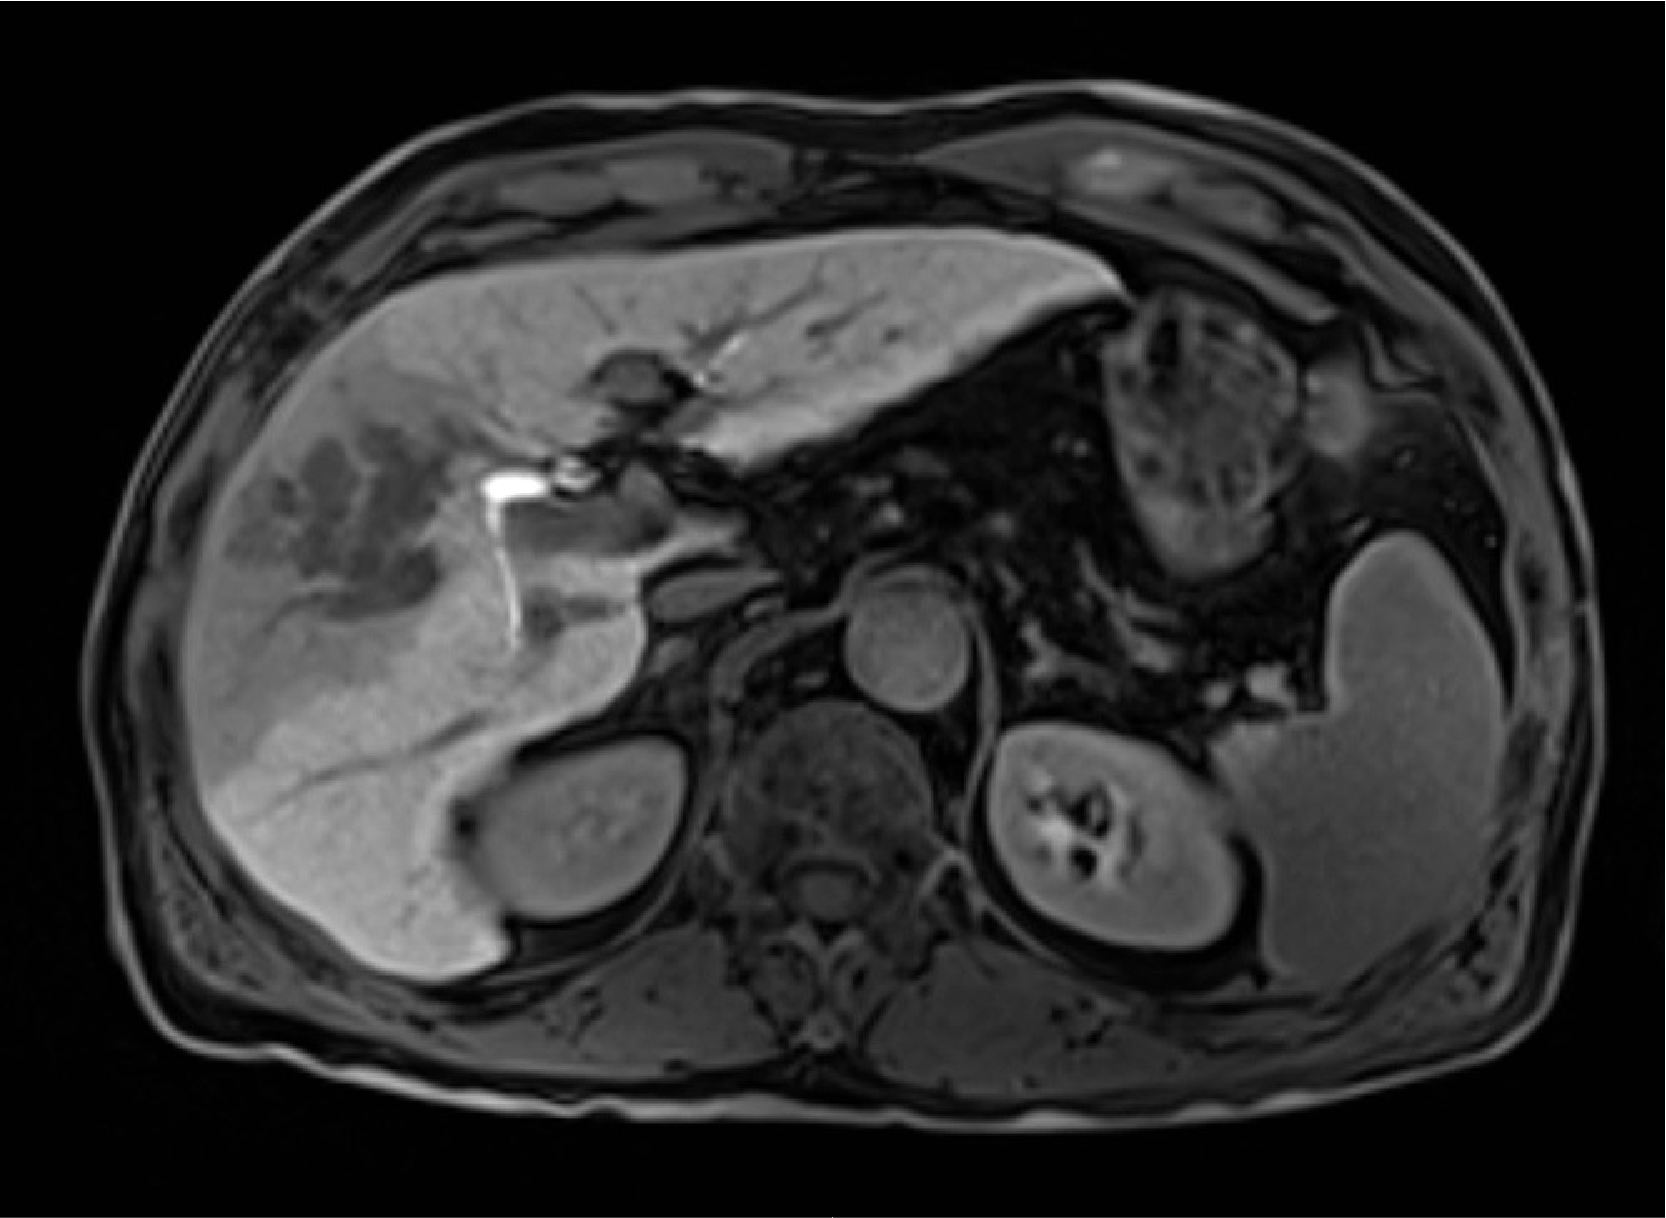

Fig. 3. Pretreatment late phase

The mass lesion in the anterior segment of the right lobe of the liver showed a homogeneous low signal, and no heterogeneously high-signal region was found.

Fig. 4. Pretreatment hepatobiliary phase

Although part of the portal vein tumor embolism remained, the mass in the anterior segment of the right lobe of the liver showed marked reduction in size.

Fig. 5. Hepatobiliary phase after four treatment cycles